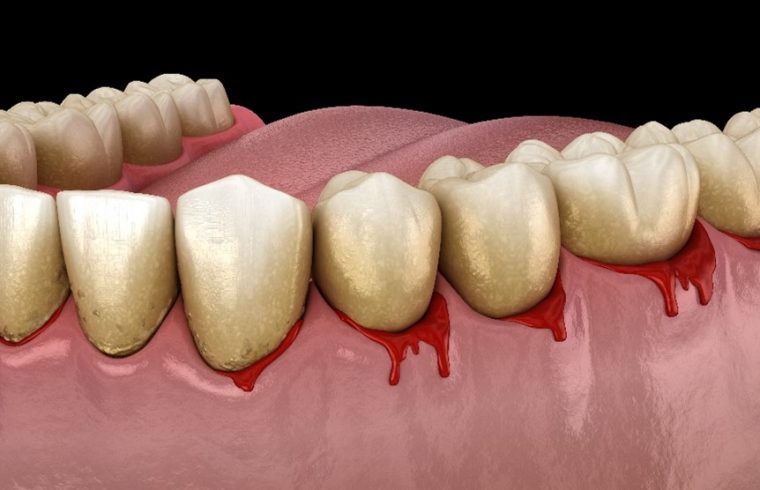

歯ぐきから出血をしているイメージイラスト

歯周病とは、歯と歯ぐき周りの組織に炎症が起こる慢性的な口腔疾患の一つです。歯周組織が炎症を起こし、歯の周りの歯ぐきや歯を支えている骨が溶けてしまう病気です。進行すると歯と歯ぐきの間に深い溝(歯周ポケット)ができます。歯周ポケットの中で細菌が増殖し、歯周病はさらに悪化します。

2. 歯磨きや食事の際、歯ぐきから出血がある